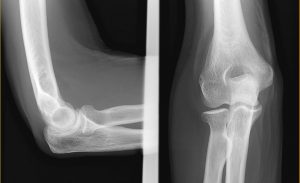

Fracture de la tête radiale droite

Femme de 60 ans, bilan d’extension d’une néoplasie mammaire. Notion de chute il y a 10 jours.

Hyperfixation intense, isolée, focalisée de la tête radiale droite évoquant une fracture confirmée sur la radiographie standard.